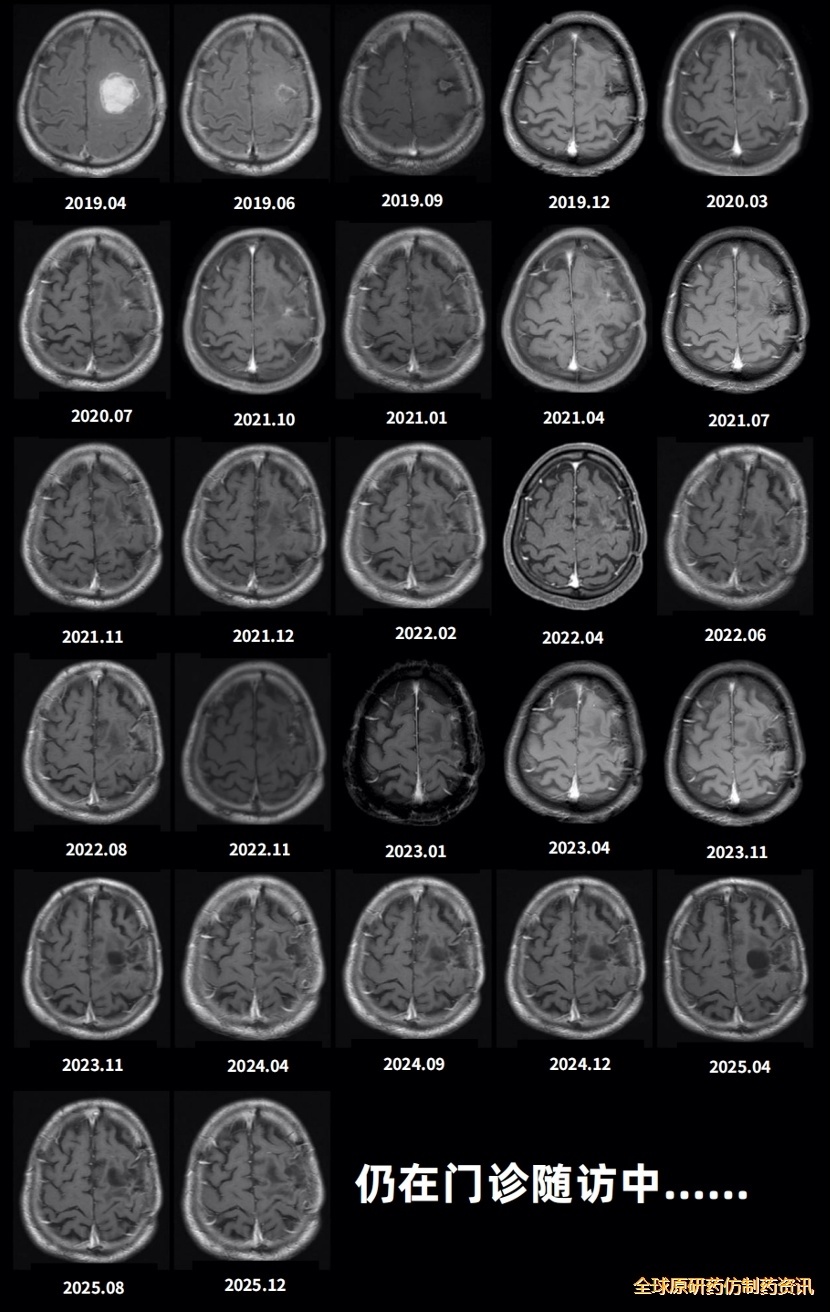

后续治疗期间,定期每2-3个月门诊复查头部增强MRI扫描(图6)。2022年8月首次提示可疑复发,11月复查确认,遂再次启用TMZ化疗,继续采用5/28方案,每周期连续服药5天,共完成12周期。截至2026年2月27日随访,影像学显示肿瘤未见复发,生存时间超过7年。患者目前KPS评分90分,生活可自理,行走稳定,坚持早睡早起及适量运动,心态积极乐观,整体状态良好。

图5.患者术后门诊定期复查MRI影像